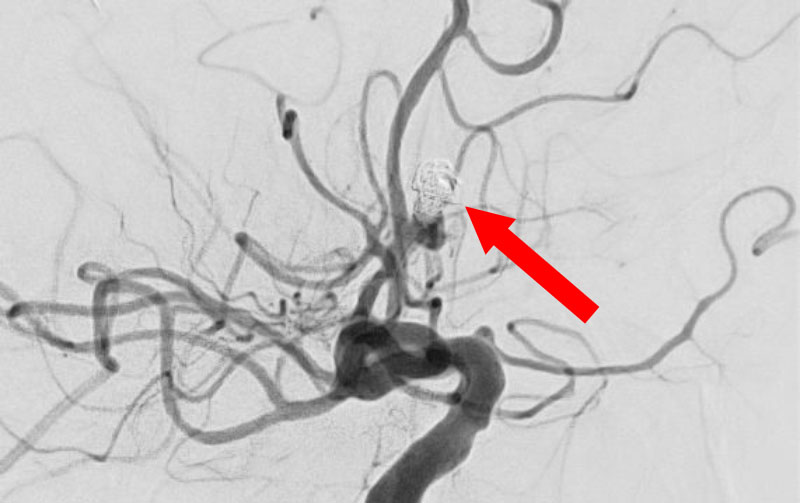

'25年10月

くも膜下出血

前交通動脈瘤破裂

40代

大阪府の病院

No.1589 手術前

No.1589 手術中

No.1589 手術後